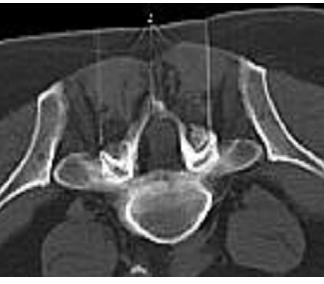

Sacral block, peridural block

I fit comes to a peridural or scral block the surgeon infiltrates and floods the nerve root in the area of the lower lumbal spine. With the help of a small entrance the surgeon will place a small canula or catheter in close relation to the dural sack through which an anesthetic gets applied.

We try to block the lower lumbal and sacral nerve roots which can be irritated after an slipped disk or a stenosis. The pain and the swelling need to be reduced. Empirically we have a succeed rate of 60- 70%. It is necessary to perform 6- 12 injections in alternating periods.